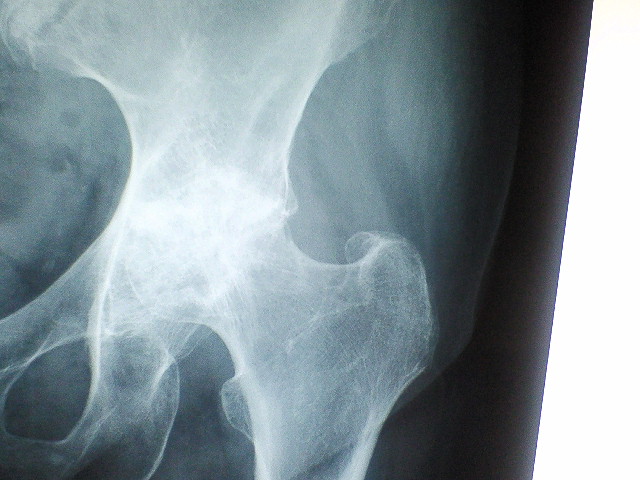

股関節の手術。。

右を手術したのは4年前だった。。